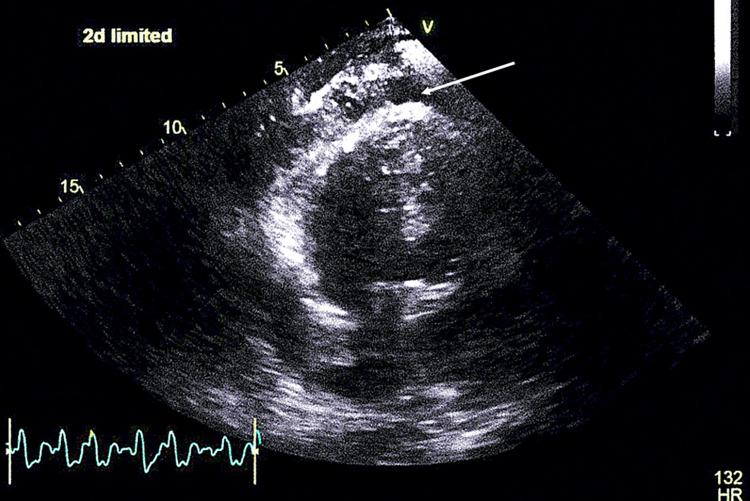

Infective endocarditis (IE) is a microbial infection affecting cardiac valves. IE most often affects the aortic valve and is commonly caused by community-acquired, penicillin-sensitive streptococcus that enters through the oral cavity. In this report, we present a case of a 66-year-old man with a medical history of congenital pulmonic stenosis status after pulmonic valve (PV) repair. The patient underwent a transesophageal echocardiogram showing a 1 cm × 0.7 cm mobile vegetation attached to the ventricular aspect of the right coronary aortic cusp and a 1.1 cm × 0.5 cm mobile vegetation attached to the arterial aspect of the PV cusp. In conclusion, concomitant right- and left-sided IE is an exceedingly rare condition. Due to its rarity and complexity of presentation, pulmonic valve endocarditis (PVE) requires a multidisciplinary approach to its perioperative management to prevent systemic complications.

感染性心内膜炎(IE)是一种影响心脏瓣膜的微生物感染。IE最常累及主动脉瓣,通常由经口腔进入的社区获得性、对青霉素敏感的链球菌引起。在本报告中,我们介绍了一例66岁男性患者,其有先天性肺动脉狭窄病史,曾接受肺动脉瓣(PV)修复术。患者接受经食管超声心动图检查,显示一个1 cm×0.7 cm的活动赘生物附着于右冠状动脉主动脉瓣叶的心室面,以及一个1.1 cm×0.5 cm的活动赘生物附着于PV瓣叶的动脉面。总之,双侧IE是一种极其罕见的情况。由于其罕见性和临床表现的复杂性,肺动脉瓣心内膜炎(PVE)需要多学科方法进行围手术期管理,以预防全身并发症。